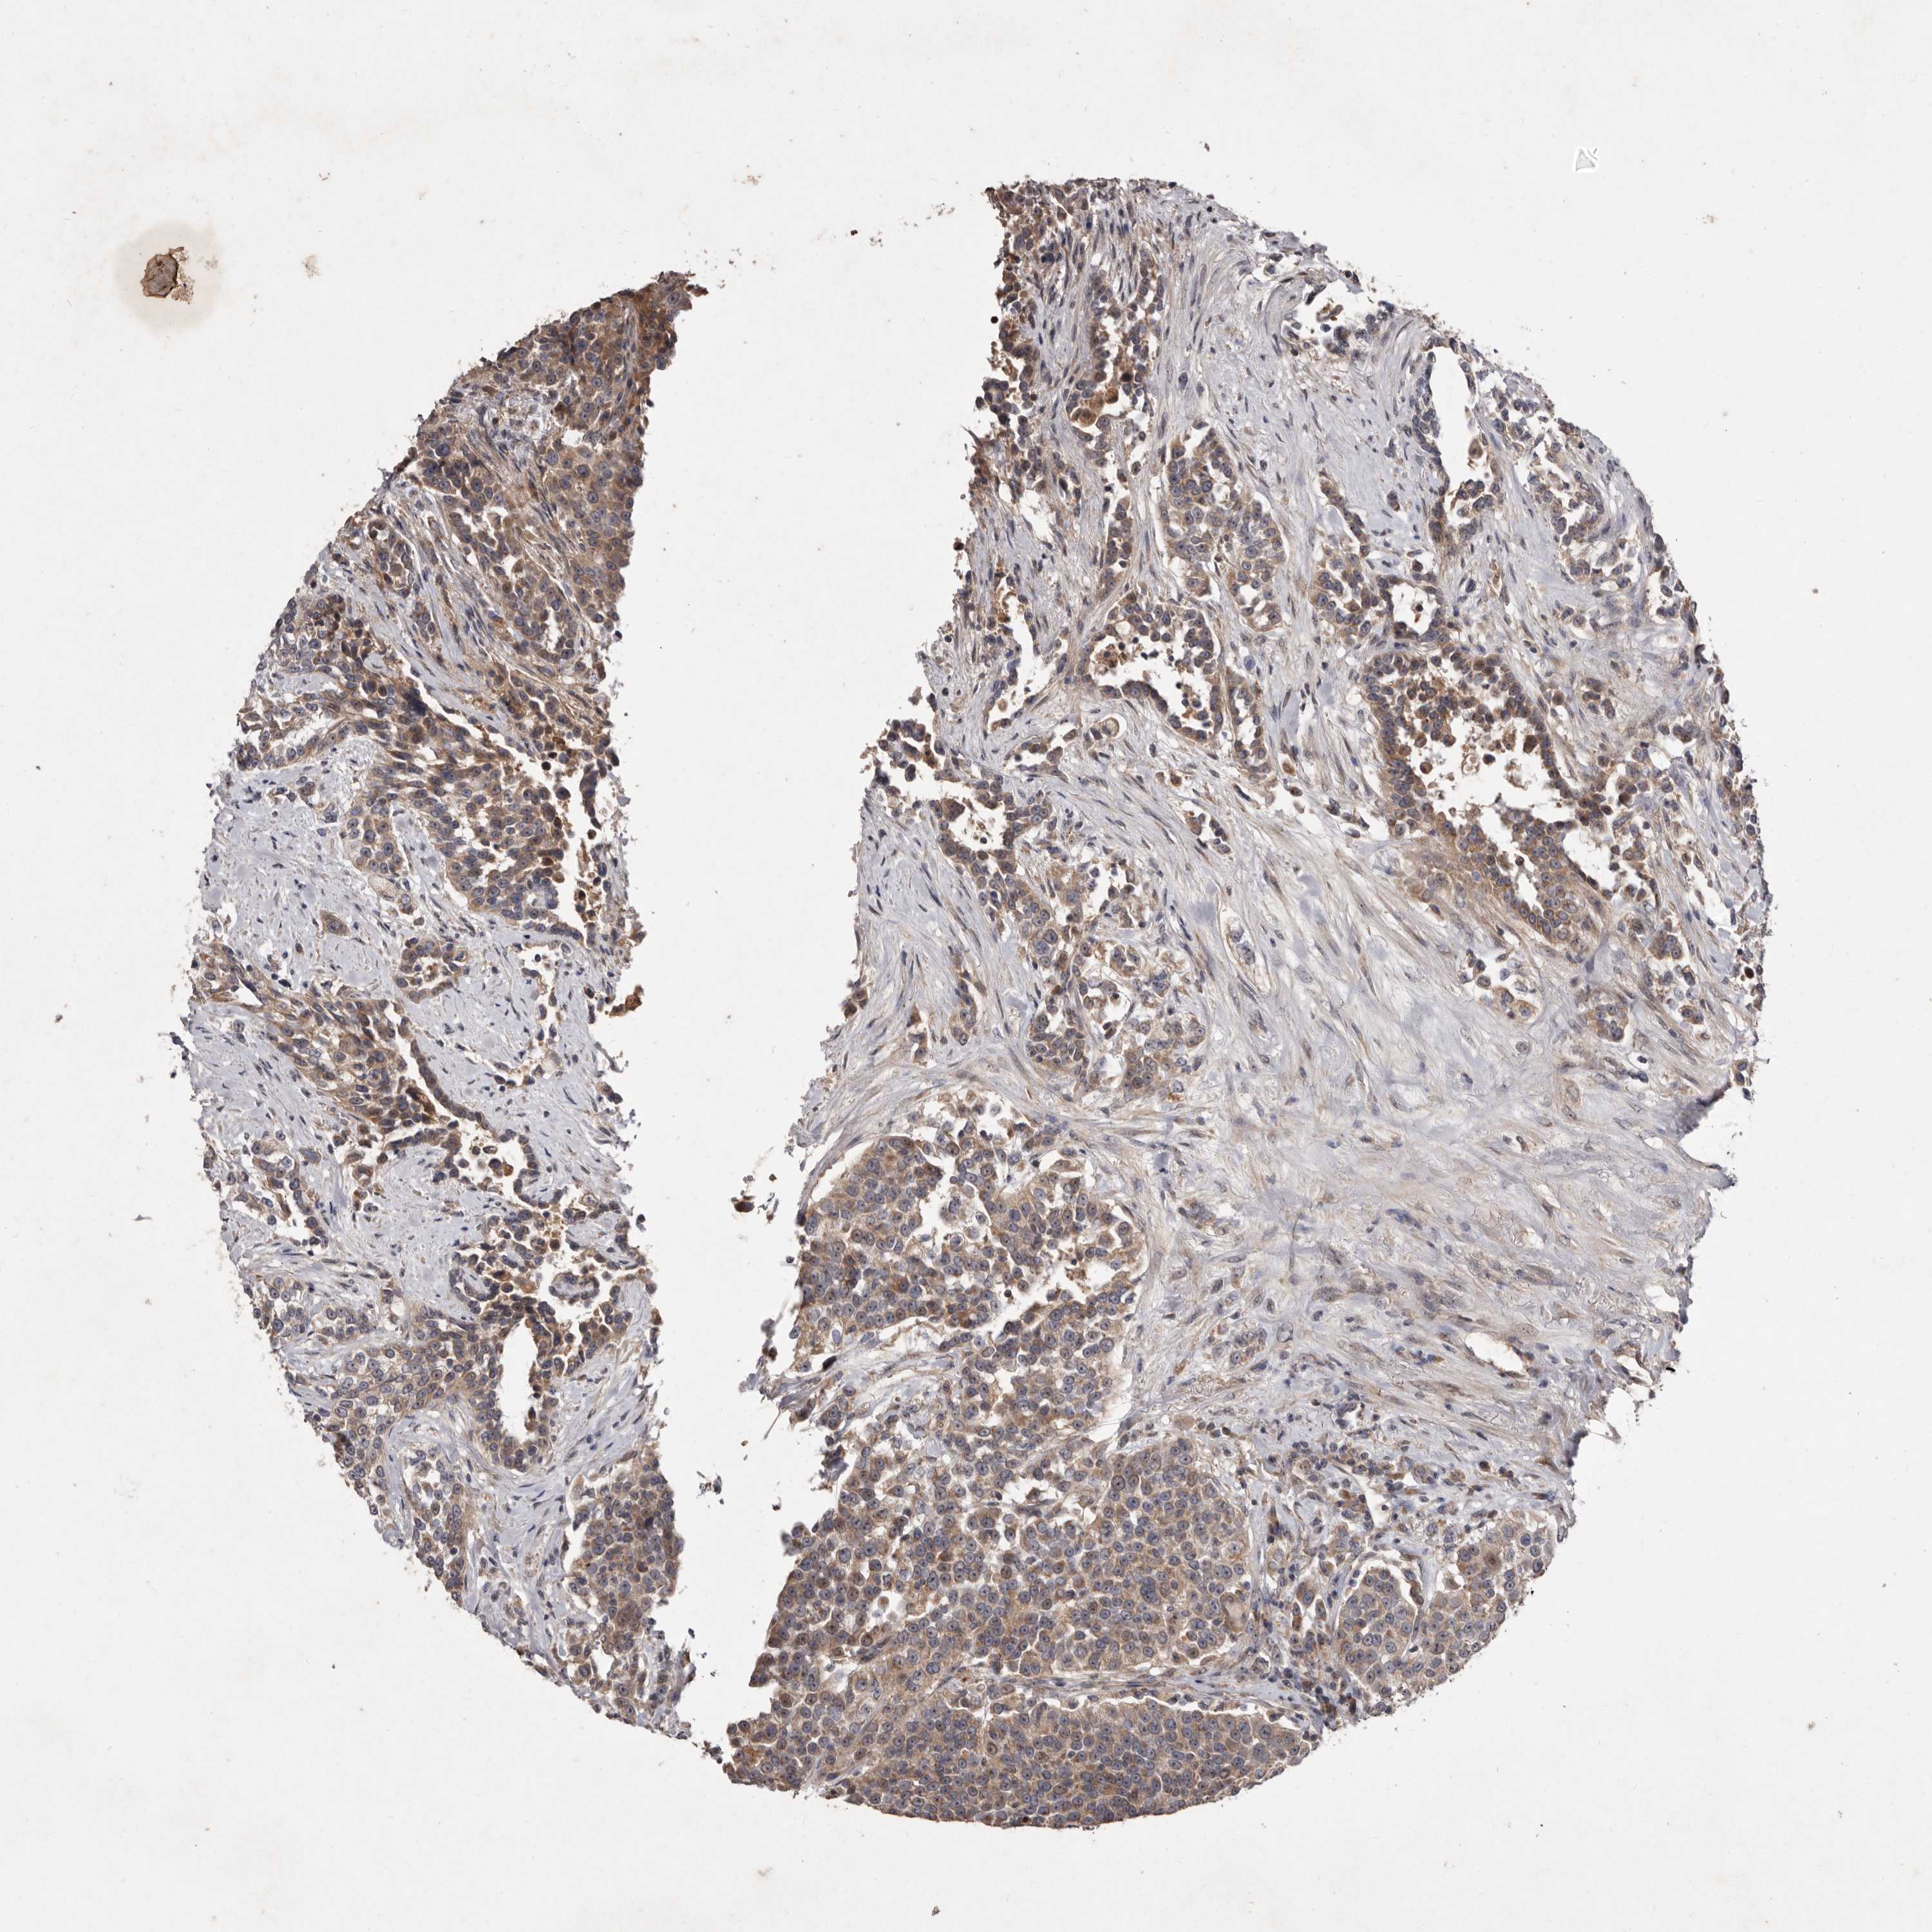

UROTHELIAL CANCER - Protein expressioni

A mouse-over function shows sample information and annotation data. Click on an image to view it in a full screen mode. Samples can be filtered based on level of antibody staining by selecting one or several of the following categories: high, medium, low and not detected. The assay and annotation is described here.

Note that samples used for immunohistochemistry by the Human Protein Atlas do not correspond to samples in the TCGA dataset.

Antibody stainingi

Antibody staining in the annotated cell types in the current human tissue is reported as not detected, low, medium, or high, based on conventional immunohistochemistry profiling in selected tissues. This score is based on the combination of the staining intensity and fraction of stained cells.

Each image is clickable and will lead to virtual microscopy that enables deeper exploration of all samples and also displays staining intensity scores, fraction scores and subcellular localization as well as patient and tissue information for each sample.

Antibody HPA028476

Antibody HPA028486

Antibody HPA028563

Staining

High

Medium

Low

Not detected

Intensity

Strong

Moderate

Weak

Negative

Quantity

>75%

75%-25%

<25%

None

Location

Nuclear

Cytoplasmic/membranous

Cytoplasmic/membranous,nuclear

Urothelial carcinoma, Low grade

Urothelial carcinoma, High grade